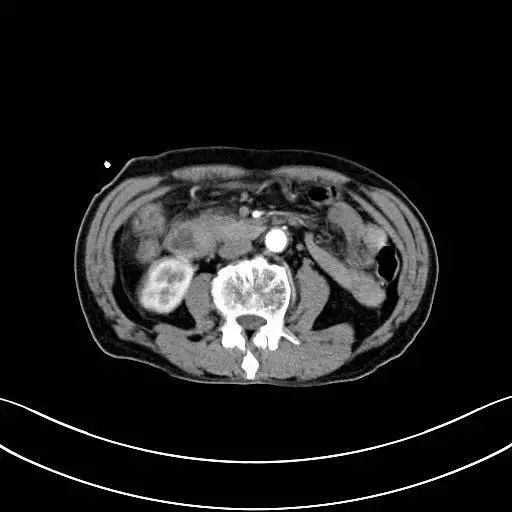

2019年9月25号,暨南大学附属复大肿瘤医院接到一位因腹部疼痛入院治疗的患者,姓龚,江西宜都人,79岁高龄,以前曾在林场当测量工。入院通过了解,知道此患者曾在2019年9月19日-江西省于都县人民医院-腹部CT检查结果提示:胃窦部壁增厚,胆总管及主胰管轻度扩张,提示下段梗阻可能,当地医生为患者做过胆囊引流处理。通过详细的检查,龚先生被诊断为十二指肠壶腹部腺癌、上消化道梗阻。

金医生:十二指肠壶腹部腺癌起源于十二指肠乳头及乳头附近的黏膜、壶腹内的黏膜、胰管及胆总管十二指肠壁间部黏膜上皮。大部分患者早期无明显临床症状,出现症状入院检查的患者病情大部分都为中晚期。十二指肠壶腹部腺癌根治性手术难度主要在于手术切除范围大,术中吻合复杂,术后可能出现并发症多且一旦出现术后并发症就可能危及生命。龚先生入院后,我们也曾建议过行肿瘤根治性手术,但由于龚先生年纪较大,家属担心他无法耐受较大手术,不考虑行根治性手术。结合家属的要求和龚先生入院后的病情,我们综合考虑相关治疗方案,最终在杨波副主任医师和我院肿瘤外科医师共同努力下在2019年10月8日顺利完成了全麻下“胆肠吻合+胃空肠吻合+空肠R-Y吻合术”。

十二指肠壶腹部腺癌情况